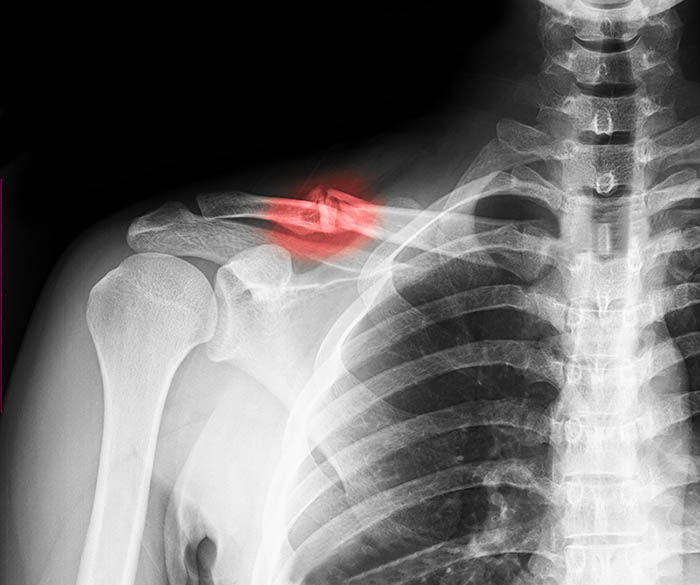

Первым шагом в диагностике является рентгенографическое исследование. Снимок поможет определить степень и характер травмы. Не стоит переживать: даже серьезные переломы с смещением у маленьких пациентов заживают достаточно быстро.

После получения рентгеновских снимков врач решит, будет ли лечение амбулаторным или потребуется госпитализация. Если обнаружится смещение отломков или открытый перелом, ребенка направят в стационар.